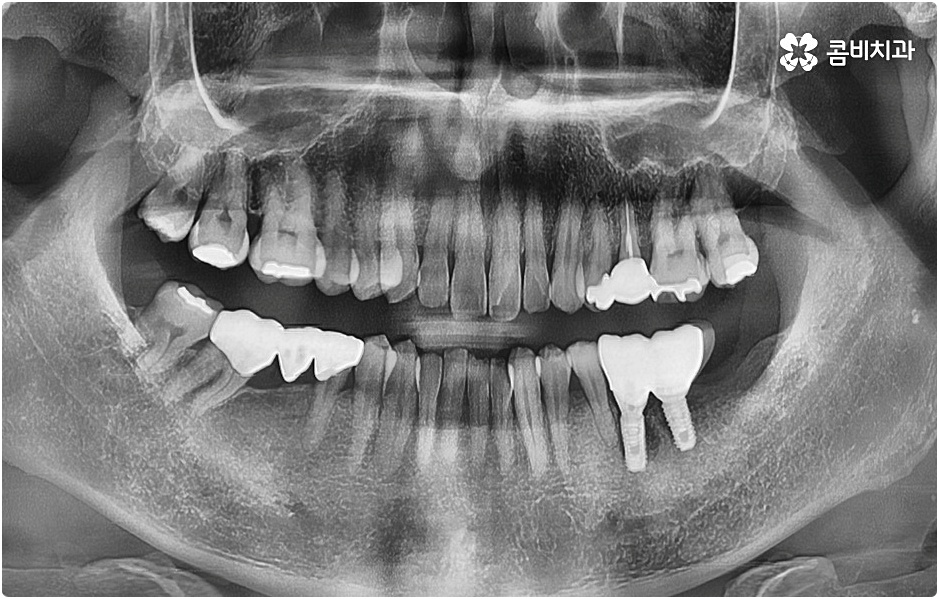

임플란트 시술을 받을 때 치아를 상실한 원인이 무엇인지, 상실하고 나서 그대로 둔 시간이 얼마나 되는지, 현재 치아나 잇몸 등 구강 내부 상황이 어떤지 등등을 먼저 꼼꼼하게 파악할 필요가 있는데요. 예를 들어 20대임플란트 를 받게 된 원인이 사고와 같은 외부 충격으로 인한 것이고 시간이 많이 흐르지 않은데다 다른 구강 질환 (충치나 치주 질환) 이 크게 문제가 되지 않는 상황이라면 젊은 나이이기 때문에 바탕이 되는 잇몸뼈 건강이 비교적 양호할 것이라고 예상할 수 있으며 이런 경우 즉시 임플란트 방식을 검토해 볼 수 있어요. 면밀한 정밀 검사 후 가능하다는 의료진의 진단이 내려진다면 당일에 인공 치근을 심고 임시 크라운까지 올려 바로 사용할 수 있는 즉시 임플란트 방식을 통해 보다 빠르고 간편하게 수복을 할 수 있습니다.

그러나 나이가 젊다고 해도 만약 치아를 상실한 원인이 심각한 구강 질환으로 인한 것이거나 치아를 잃고 나서 오랜 시간 방치를 하였거나 평상시에 당뇨 또는 고혈압 등을 앓고 있었다면 환자분의 잇몸뼈 건강이 양호하지 않을 수 있으며 그런 경우에는 즉시 임플란트 시술을 받을 수 없고 먼저 뼈이식 과정을 통해서 잇몸뼈를 보충해 준 다음 20대임플란트 식립을 진행하는 것이 정확도와 지속성을 높여주는 방법이라고 할 수 있어요.

또한 20대임플란트 의 경우 남은 생 동안 인공 치아의 도움을 받아야 하는 기간이 보다 긴 만큼 빠른 속도 자체 보다는 식립의 정확성과 성공률, 지속적인 안정성 및 수명 등에 좀 더 초점을 맞출 필요가 있으므로 자신의 상황을 꼼꼼하게 검진 받고 그에 맞는 치료를 무리하지 않게 받으시길 권유드리고 있어요.